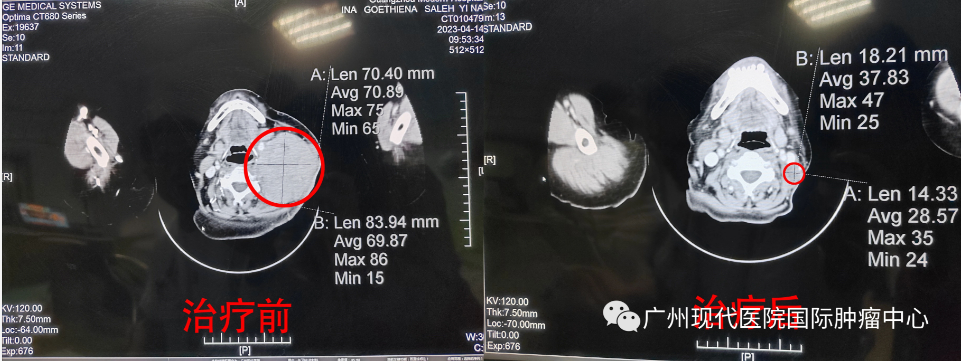

5月7号,医生按照既定的治疗方案,为依娜进行了第2轮的动脉灌注介入治疗,29号做CT检查评估,结果显示左颈部肿块影(20X35mm),较前明显减小,左颈内动脉受压内移较前缓解;原右肺中叶少许斑片影,现已消失。对比4月来院治疗前的CT显示结果(颈部淋巴瘤大小86X63mm),计算肿瘤缩小87%,颈部肿块肉眼看几乎已经消失。